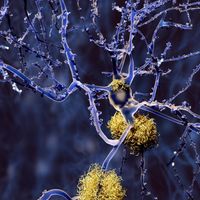

Deficient DNA Repair Mechanism May Contribute To Alzheimer’s

Deficient DNA Repair Mechanism May Contribute To Alzheimer’s